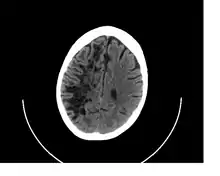

![]() A perivascular space as seen on CT | |

In humans, perivascular spaces surround arteries and veins can usually be seen as areas of dilatation on MRI images. While many normal brains will show a few dilated spaces, an increase in these spaces may correlate with the incidence of several neurodegenerative diseases, making the spaces a topic of research.[4]

Perivascular spaces are most commonly located in the basal ganglia and white matter of the cerebrum, and along the optic tract.[13] The ideal method used to visualize perivascular spaces is T2-weighted MRI. The MR images of other neurological disorders can be similar to those of the dilated spaces. These disorders are:[7]

Perivascular spaces are distinguished on an MRI by several key features. The spaces appear as distinct round or oval entities with a signal intensity visually equivalent to that of cerebrospinal fluid in the subarachnoid space.[7][14][15] In addition, a perivascular space has no mass effect and is located along the blood vessel around which it forms.[14]